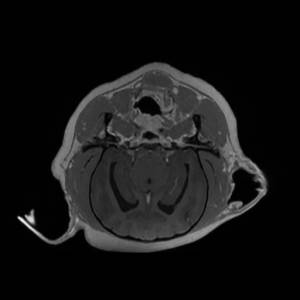

Main Gallery

Playing with a photo gallery function. It is possible to have multiple galleries, each within a namespace.